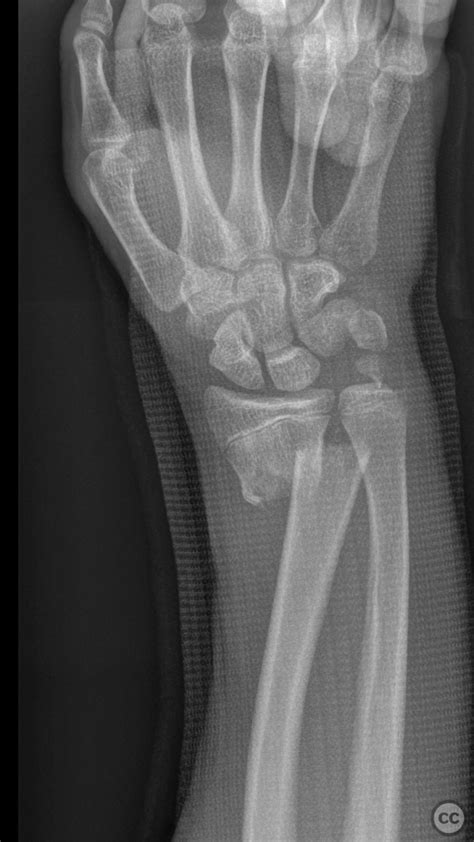

Alright, let’s kick things off by really understanding what we’re up against when we talk about distal radius fractures . These aren’t just any old broken bones; they’re incredibly common, making up a huge chunk of all fractures treated in emergency rooms worldwide. Typically, they happen when you try to break a fall with an outstretched hand, sending all that impact force right up your arm to your wrist. Think about slipping on ice, falling off a bike, or even just a clumsy step – bam , your wrist takes the hit. What’s especially tricky about distal radius fractures is the complex anatomy of the wrist joint. It’s not just a simple hinge; it’s a marvel of engineering with multiple small bones and ligaments all working together for a huge range of motion. When the distal radius, which is the larger of the two forearm bones and crucial for wrist movement, breaks, it can disrupt this delicate balance. We often categorize these fractures by patterns: Colles fractures , where the bone breaks with the fragment tilting upwards (dorsally); Smith fractures , which are less common, where the fragment tilts downwards (volarly); and Barton fractures , which involve the joint surface itself, sometimes with dislocation. Each type presents its own unique challenge, but they all share the common goal of needing precise reduction and stable fixation to ensure a good functional outcome. The AO classification system , which is a comprehensive way to describe fractures based on location, severity, and joint involvement, helps surgeons speak a common language and plan treatment strategies more effectively. Knowing these classifications helps us appreciate why a tailored approach, like the Kapandji technique, is often necessary. Without proper management, these fractures can lead to long-term pain, stiffness, and even arthritis, significantly impacting a person’s quality of life. That’s why getting it right the first time is so crucial, and why techniques like Kapandji’s have become so valuable in the orthopaedic toolkit. The challenge with these injuries isn’t just getting the bones to stick back together; it’s about restoring the intricate biomechanics of the wrist so that patients can regain their full range of motion, grip strength, and overall function. It’s a big ask, but with the right approach, it’s totally achievable.

So, what’s the real magic behind the Kapandji technique and why does it stand out among the myriad of options for treating distal radius fractures ? At its core, the Kapandji technique, developed by the French orthopaedic surgeon Dr. André Kapandji, is an intrafocal pinning method. This means we’re not just stabilizing the fracture from the outside, but actually inserting small, flexible K-wires (Kirschner wires) into the fracture site itself to gently push the bone fragments back into their anatomical position. Think of it like a subtle internal scaffolding that levers the broken pieces back into place, restoring the correct length, alignment, and angulation of the bone. This approach is particularly brilliant because it allows for an anatomic reduction – getting the bones aligned just as they were before the injury – with minimal soft tissue disruption. Unlike more extensive open surgeries that might involve large incisions and significant stripping of muscle and periosteum (the membrane covering the bone), Kapandji is relatively minimally invasive . This often translates to less pain post-operation, a reduced risk of infection, and potentially faster healing times. The key principle here is achieving stable fixation that allows for early mobilization , which is a huge advantage for patient recovery. While some techniques might require prolonged immobilization, the Kapandji method, when indicated, aims to provide enough stability for the patient to start gentle wrist movements sooner, preventing stiffness and promoting quicker return to function. This emphasis on early motion aligns perfectly with modern orthopaedic philosophies, including many of the AO principles , which prioritize biological healing and functional recovery. It’s a smart balance between stability and biological friendliness. Compared to other techniques like external fixation, which can be cumbersome and have their own set of complications like pin-tract infections, or traditional plating, which involves more extensive dissection, Kapandji offers a unique middle ground. It’s particularly well-suited for certain types of unstable, extra-articular (outside the joint) or simple intra-articular (inside the joint) distal radius fractures where maintaining reduction is the primary challenge. The real genius lies in using the wires as internal joysticks, maneuvering the fragments under fluoroscopic guidance to achieve that perfect alignment. It’s a testament to how intelligent, biomechanically sound surgical design can make a profound difference in patient outcomes, offering a less invasive yet highly effective path to recovery. This technique truly underscores the idea that sometimes, less is more, especially when it comes to getting broken bones back in working order. Choosing Kapandji often means choosing a quicker, smoother path back to daily activities for the patient.

Alright, let’s pull back the curtain and see exactly what goes down during a Kapandji technique procedure for a distal radius fracture . This isn’t just about sticking wires in; it’s a meticulously planned surgical journey designed to achieve optimal results. First up, pre-operative planning is paramount. This involves a thorough assessment of the patient, understanding their medical history, and, most importantly, getting high-quality imaging – X-rays, and sometimes a CT scan – to fully appreciate the fracture pattern. Surgeons will meticulously analyze the displacement, angulation, and involvement of the joint surface. This helps determine if Kapandji is the best fit and how many pins will be needed and their ideal trajectory. Once the decision is made, the patient is prepared for surgery. Anesthesia is typically regional (like a nerve block) or general, ensuring the patient is comfortable and pain-free. The patient is usually positioned supine (on their back) on the operating table, with the arm extended on a hand table, allowing full access to the wrist. Crucially, a tourniquet is applied to the upper arm to create a bloodless field, which significantly improves visibility for the surgeon. Now, the real artistry begins with reduction maneuvers . This involves gentle traction applied to the hand, often manually, to distract the fracture fragments. The surgeon then uses specific manual manipulations, sometimes with the help of a bone clamp or K-wire, to restore the correct length and alignment of the distal radius. This is often done under fluoroscopic guidance – a real-time X-ray machine – which acts as the surgeon’s eyes, ensuring every manipulation is precise. Once a satisfactory reduction is achieved, it’s time for pin insertion . This is where the Kapandji technique truly shines. Typically, two to three small K-wires are inserted percutaneously (through small skin punctures, avoiding large incisions). The entry points are usually on the dorsal (back) or radial (thumb side) aspect of the wrist, depending on the fracture pattern. The wires are advanced into the fracture site itself , acting as levers or